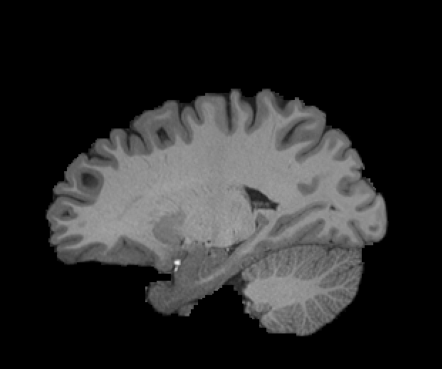

Inverse consistent rigid, affine, nonparametric, and MLP registration. We train networks on MNIST 5s using the methods in Secs. 3 and 4, demonstrating that the resulting networks are inverse-consistent. Our TwoStepConsistent (TSC) operator can be used on any combination of the networks defined in Sec. 3. For demonstrations, we join an MLP registration network to a vector field registration network, and join two affine networks to two vector field networks. Fig. 2 shows successful inverse-consistent sample registrations.

| Moving Image | Warped Image | Fixed Image | Moving Image | Warped Image | Fixed Image |